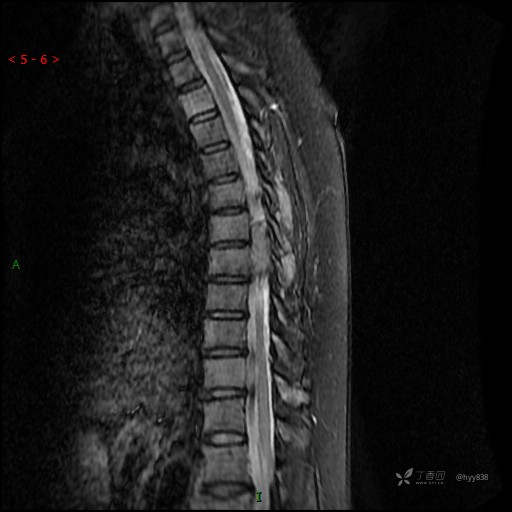

MRI SAG T2WI+T1WI